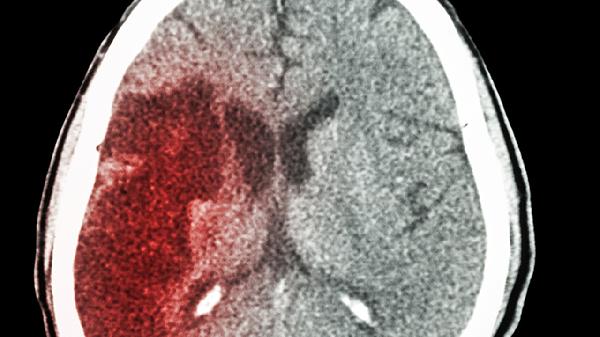

主要成分包括黄芪、赤芍、丹参等,具有益气活血、化瘀通络作用。通过改善脑部微循环、降低血液黏稠度,预防脑梗复发。服用时需注意与降压药的协同作用,定期监测血压变化。

提取自银杏叶标准提取物,含黄酮类和萜类活性成分。具有清除自由基、改善脑血流、抑制血小板活化因子等作用,适用于慢性脑供血不足患者。需警惕与抗凝药物合用可能增加出血风险。